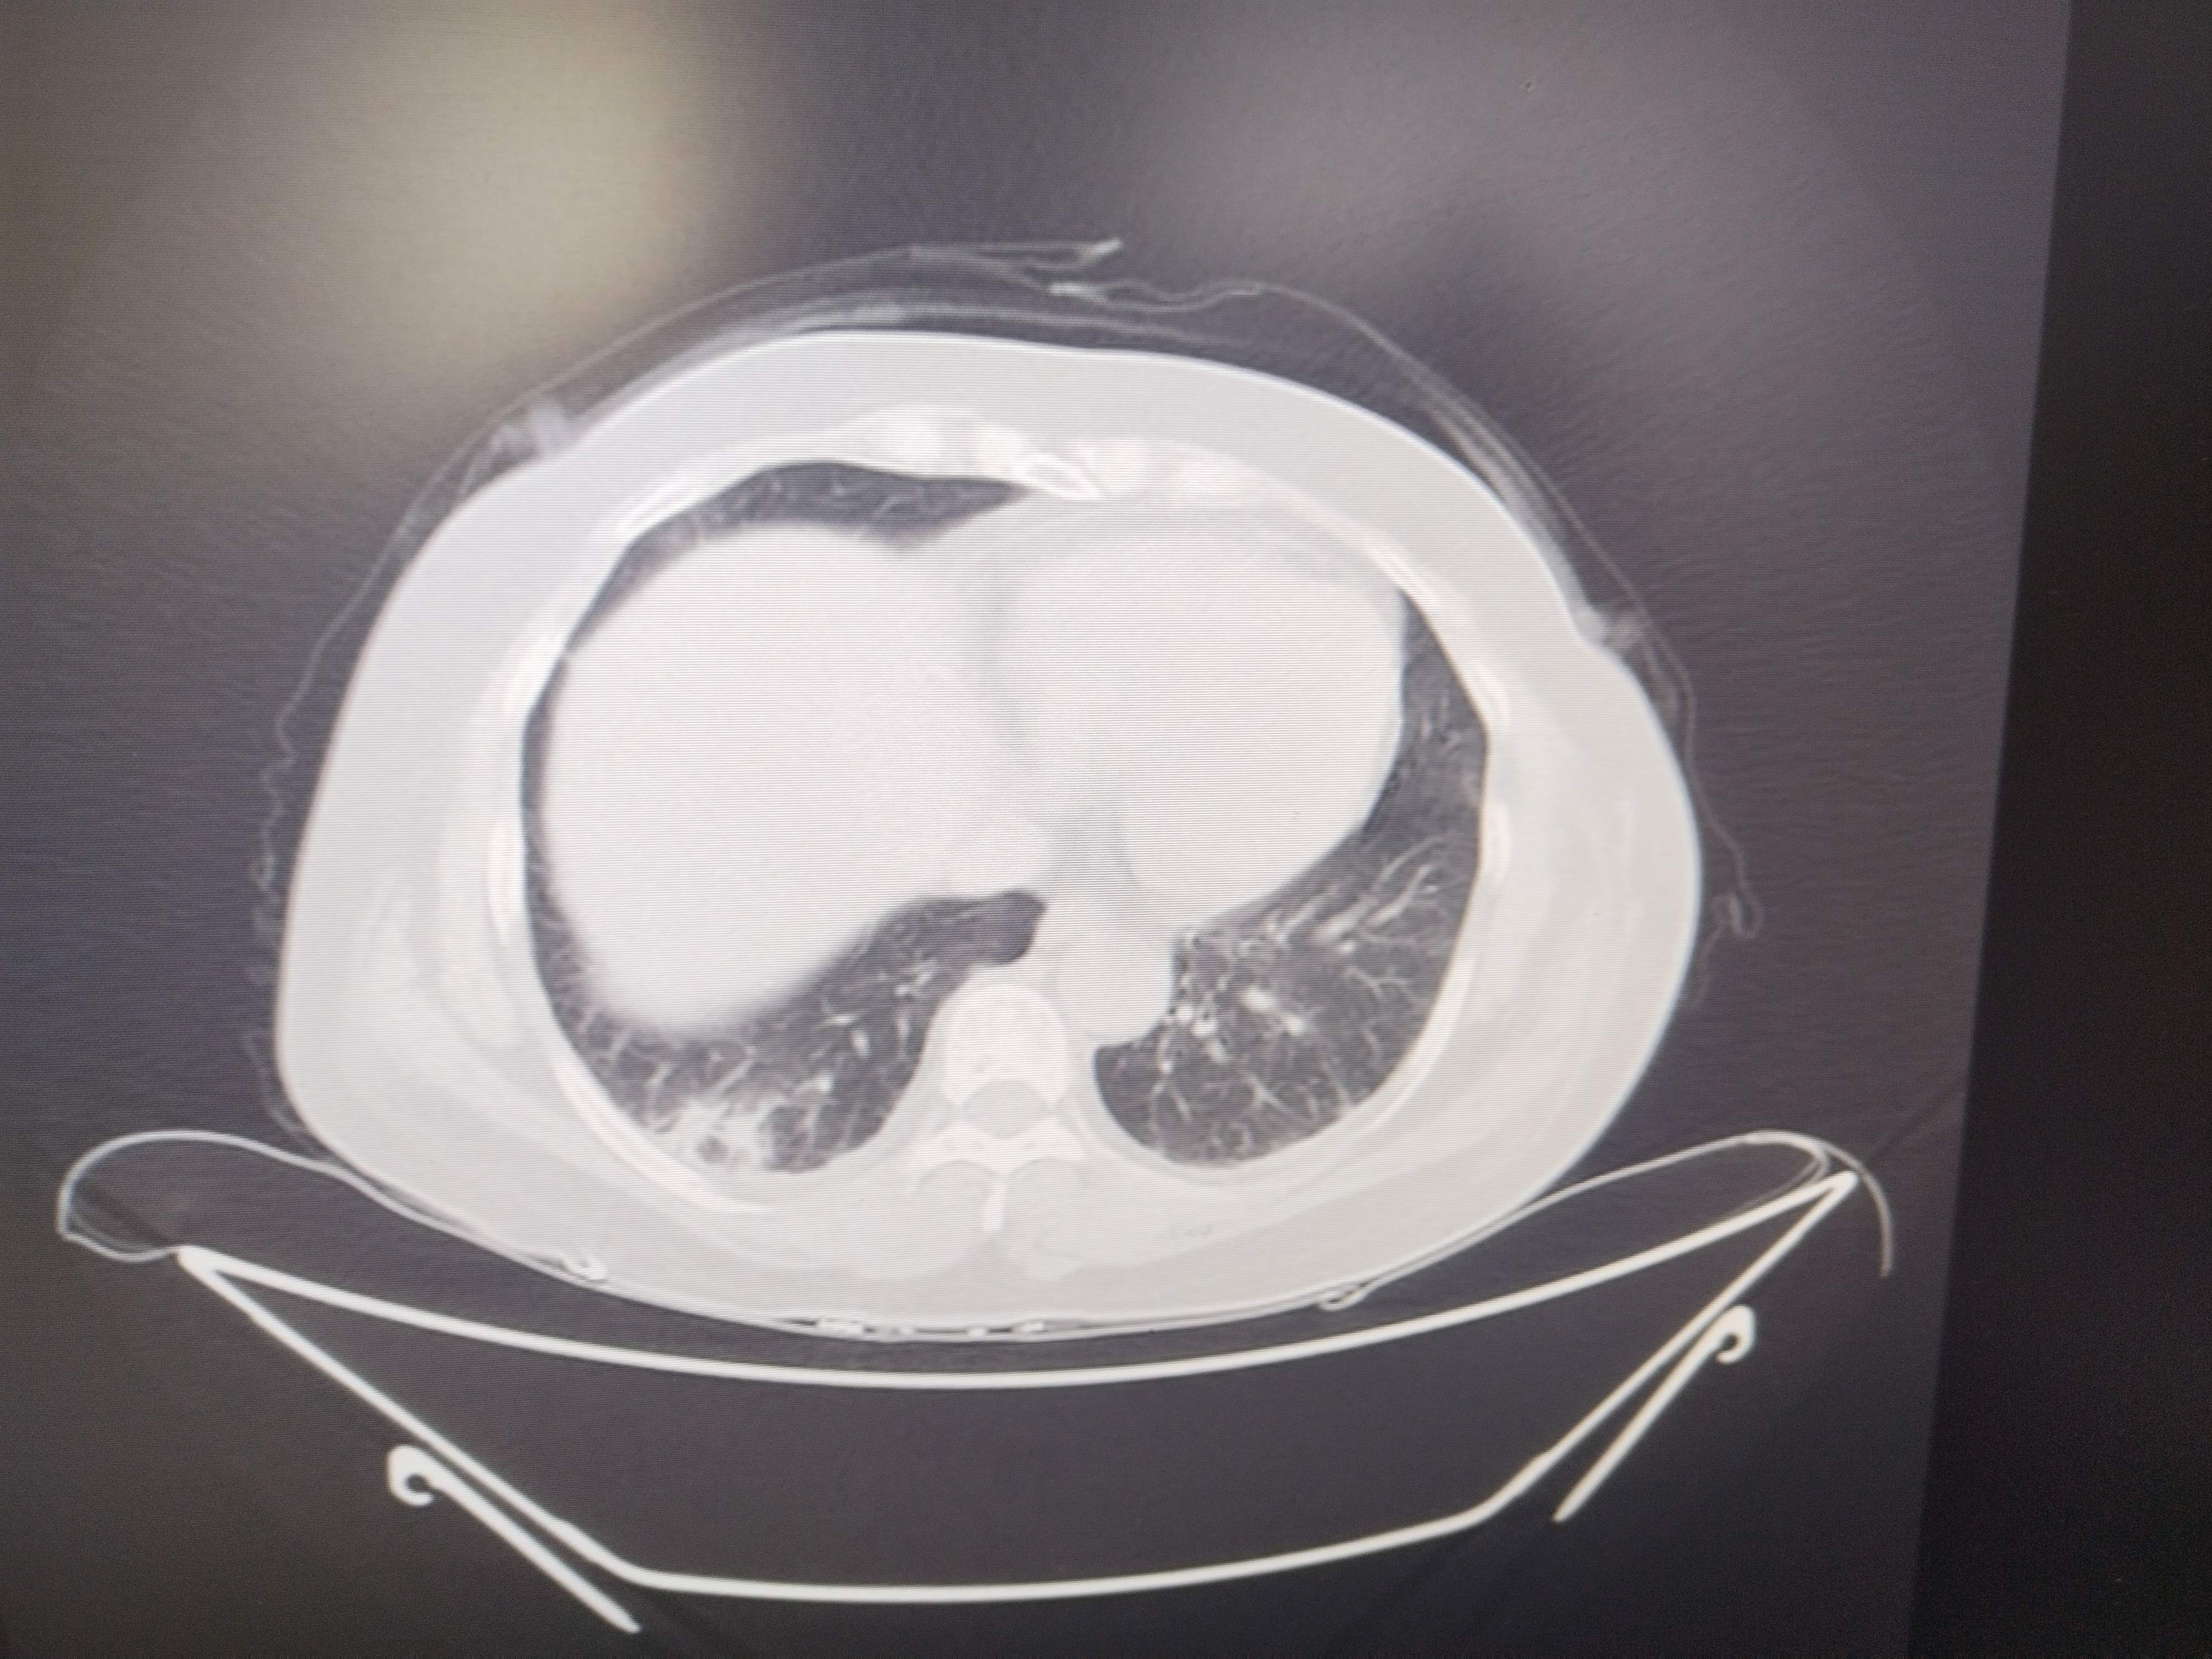

四肢肌无力伴有肌肌酸激酶升高。

患者女性,54岁,

主诉:四肢肌肉酸痛伴无力半个月,加重1天

现病史:半个月前无明显诱因出现双下肢肌肉酸痛,后出现双上肢肌肉酸痛,伴无力,伴活动受限,不能自行抬起、行走困难,伴肩背部疼痛,伴双眼睑、面部水肿,呈持续性,伴面部红斑,小便无泡沫,尿量无改变,无尿频、尿急、尿痛,无双下肢水肿,无恶心、呕吐,无心慌、胸闷,前往“当地医院”查心电图(2025-04-16):1、窦性心动过速2、T波异常 (可能是下壁心肌缺血)心肌酶谱(2025-04-16):血清肌酸激酶:8736U/L乳酸脱氢酶727U/L肌酸激酶同工酶52.18ng/mL心肌酶谱(2025-04-18)肌酸激酶:11605U/L乳酸脱氢酶620U/L;肝功(2025-04-18):丙氨酸氨基转移酶121U/L天门冬氨酸氨基转移酶429U/L谷氨酰氨基转移酶110U/L,尿常规:蛋白质+-尿潜血 2+;糖化血红蛋白(2025-04-18):8.1%;肩关节超声(2025-04-16)提示:1、肱二头肌长头腱腱鞘炎肌炎2、肩峰下-三角肌下滑囊炎,颈椎

上膜增厚。下肢肌电图未见异常,诊断为“横纹肌溶解”给予输液治疗(具体不详),症状无好转,1天前四肢肌肉酸痛伴无力症状加重,为求进一步诊治,遂来我院门诊以“1、皮肌炎2、2型糖尿病”为平诊收入我科,自发病以来,神志清,精神差,食欲差,睡眠差,大小便正常,近期体重未见明显增减。